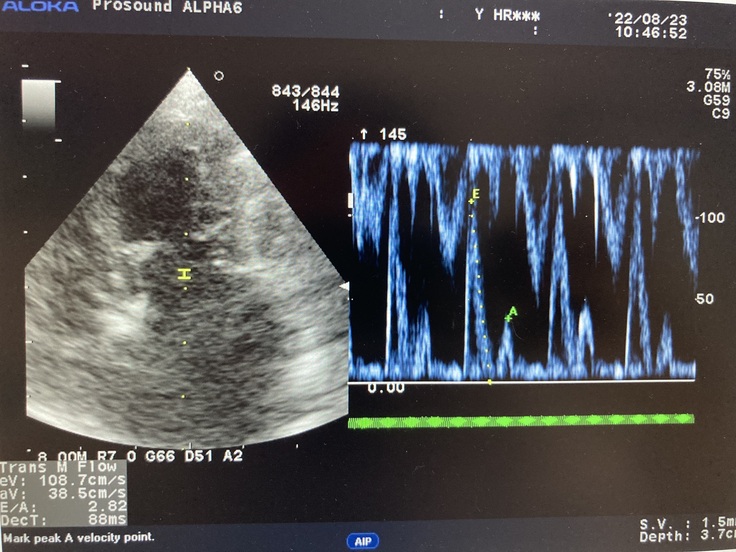

▼現在のココのレントゲンとエコー写真

心臓が大きく肥大していて

逆流も多く、かなり悪い状態で

余命6〜9ヶ月と宣告されました。